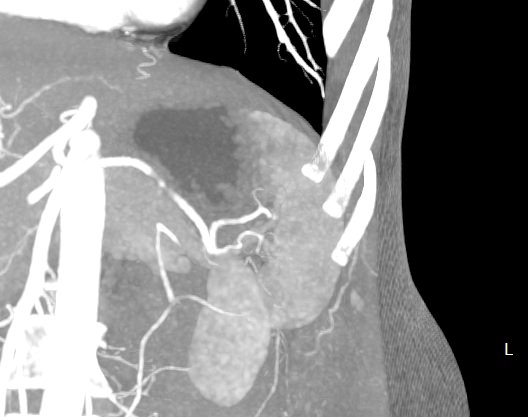

Мультиспиральная компьютерная томография селезенки – высокоинформативный лучевой метод исследования, основанный на использовании рентгеновского излучения и позволяющий детально визуализировать паренхиму селезенки, состояние близлежащих органов и тканей, питающих ее кровеносных сосудов и регионарных лимфоузлов.

МСКТ селезенки проводится как с использованием контраста, так и без него. Контрастирование применяется для выявления патологических очагов, которые могут быть не видны при нативном исследовании. Для этого внутривенно вводится контрастный препарат, содержащий йод и накапливающийся в патологических очагах опухолевой и воспалительной природы.

Мультиспиральная компьютерная томография селезенки с внутривенным болюсным контрастированием используется в диагностике гематологических заболеваний, опухолевых процессов, при планировании хирургического вмешательства и для отслеживания эффективности лекарственной терапии.

• кисты;

• доброкачественные и злокачественные опухоли, а также метастатическое поражение органа;

• сосудистые опухоли;

• кальцификаты;

• изменения воспалительного характера;

• гнойные и некротические процессы;

• нарушения кровоснабжения;

• травмы органа;

• инфаркт селезенки

• патологии сосудов.